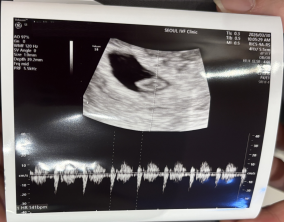

임신 수치 16, 9주차 기적의 기록

서울IVF에서는 단순히 배아 생성과 이식만 해주시는 것이 아니라, 제 생활 전반까지 신경 써주셨습니다. 휴식기에도 그저 기다리는 것이 아니라 항노화에 도움이 되는 링겔을 처방…